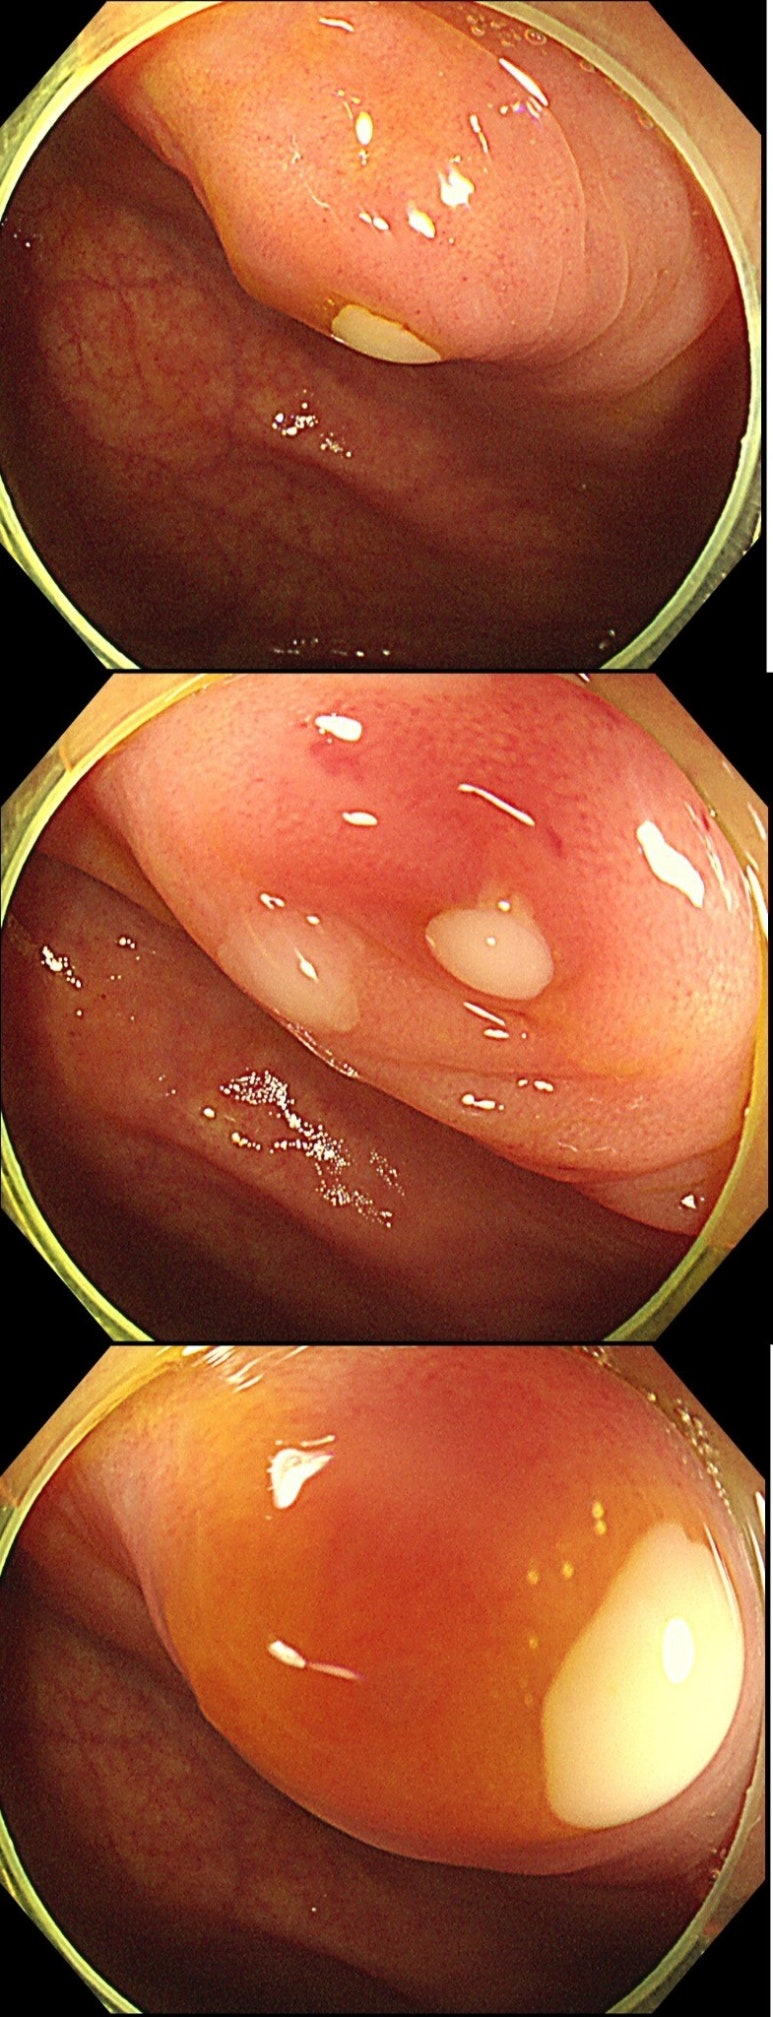

오늘은 증상이 전혀 없던 환자분의 대장내시경 검사 중

우연히 발견된 충수돌기염(맹장염) 사례를 통해

그런데 내시경 도중 우연히 맹장 개구부(appendix orifice) 부위에

고름이 동반된 염증성 변화가 관찰되었습니다.

바로 충수돌기염(appendicitis) 의심 소견이었습니다.